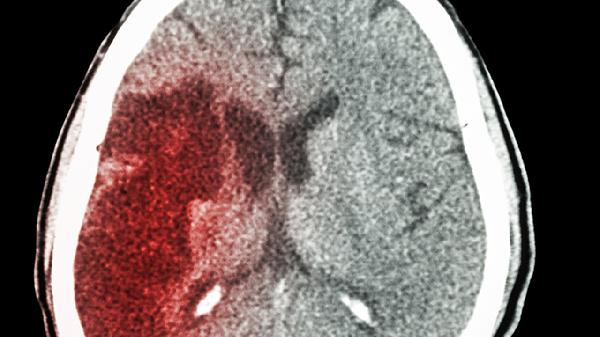

急性脑出血需立即就医,在医生指导下使用甘露醇注射液、呋塞米注射液、氨甲环酸注射液、乌拉地尔注射液、依达拉奉注射液等药物进行抢救治疗。急性脑出血起病急骤,病情凶险,自行用药可能延误救治时机。